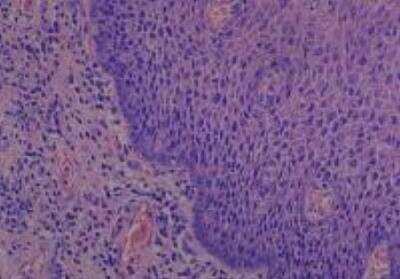

Hematoxylin & Eosin Stain: Human Common Tissue MicroArray (Normal Adjacent) [NBP2-30215] - 102. Stomach